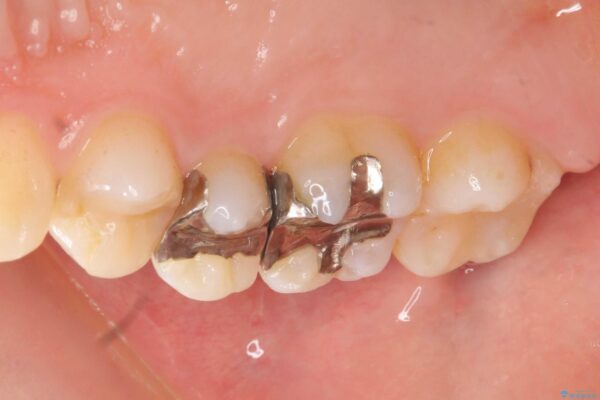

治療前

銀歯を除去してのセラミック治療[ メタルフリー ] 治療前画像 銀歯を除去してのセラミック治療[ メタルフリー ] 治療前画像 銀歯を除去してのセラミック治療[ メタルフリー ] 治療前画像